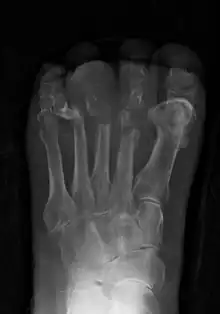

Extensive osteomyelitis of the forefoot

Radiographs and CT are the initial method of diagnosis, but are not sensitive and only moderately specific for the diagnosis. They can show the cortical destruction of advanced osteomyelitis, but can miss nascent or indolent diagnoses.[20]

Diagnosis of osteomyelitis is often based on radiologic results showing a lytic center with a ring of sclerosis.[10] Culture of material taken from a bone biopsy is needed to identify the specific pathogen;[23] alternative sampling methods such as needle puncture or surface swabs are easier to perform, but do not produce reliable results.[24][25]